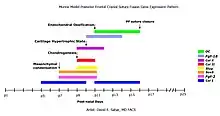

Advances in the fields of molecular biology and genetics, as well as the use of animal models have been of great importance in expanding our knowledge of suture fusion.[3] Research in animal models has led to the idea that the dura mater plays an important role in determining closure or patency of the suture.[3] In contrast to the dura mater it appears that the periosteum is not essential in causing closure or patency.[3]

Instead of describing the abnormalities in structure and form, research focuses nowadays at decoding the molecular interactions that underlie them.[3] Based on data from quantitative real-time PCR on samples of suture junctions during development, cranial suture fusion in mammals is a tightly orchestrated expression of genes in specific temporal order, leading to endochondral ossification.[37] Despite the progress that has been made, many things are still not understood about the suture biology and the exact causative pathways remain yet to be completely understood.[38]